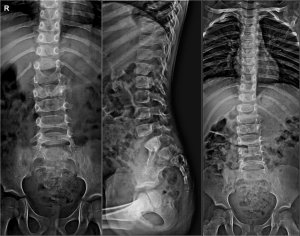

Знімок захворювання

У дорослих хірургічне лікування проводиться тільки при прояві ускладнень. Рентген та МРТ виявляють дефект хребта, про наявність якого пацієнт може не знати. Якщо діагноз поставлений, необхідно вжити заходів щодо зменшення ризику пошкодити хребет в даній області.